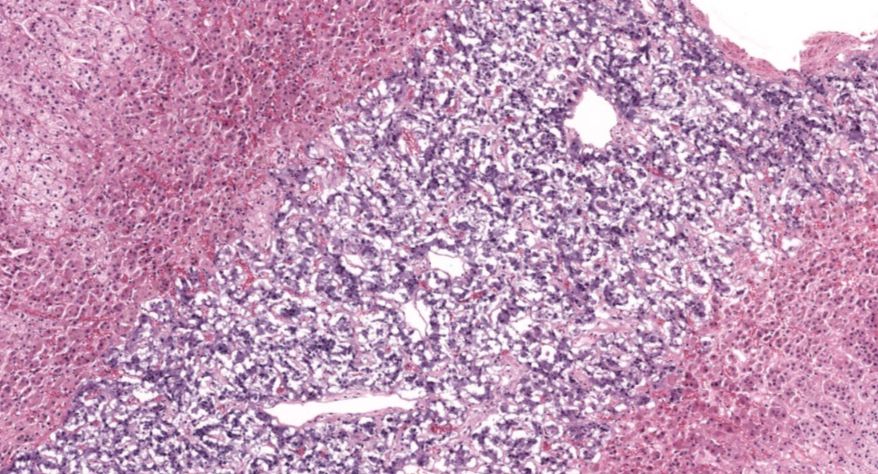

肾上腺

8.网状带(10x)

9.网状带(40x)